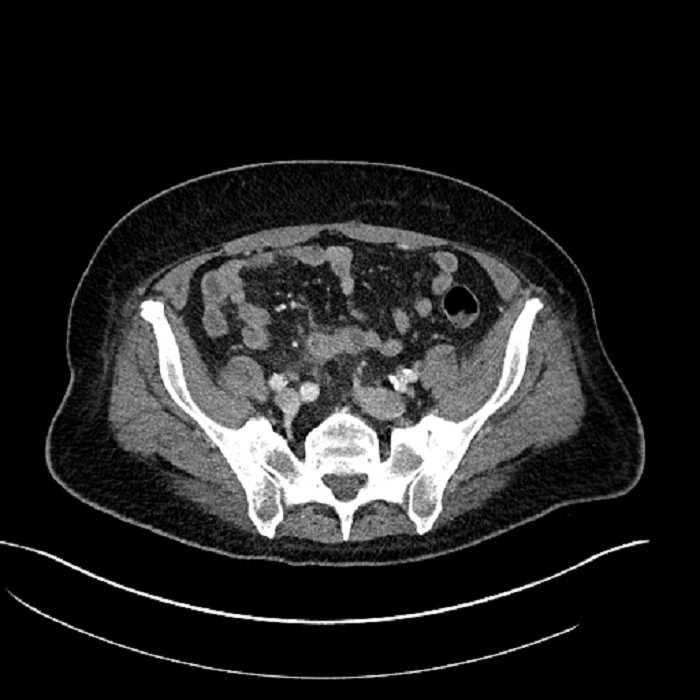

• Mild mural thickening of a segment of the sigmoid colon with adjacent fat stranding and a 1.5 cm fluid and gas collection along the tip of an inflamed diverticulum

• Loss of the normal fat plane between this collection and adjacent loops of small bowel, which demonstrate mural thickening

• No bowel obstruction

Acute sigmoid diverticulitis complicated by a small contained perforation and a large abscess in the right hepatic lobe. Additional small subcapsular abscesses along the anterior margin of the left hepatic lobe.

Additionally, loss of the normal fat plane between the peridiverticular collection and adjacent thickened loops of small bowel raises the potential for an enterocolonic fistula.

Hepatic abscess showing the double target sign with low density internally surrounded by a thin inner enhancing rim (red arrow) and ill-defined outer low density rim (yellow arrow). Blue arrow indicates an internal septation. Red arrows: additional smaller subcapsular abscesses. Red arrow: focal contained perforation associated with diverticulitis.